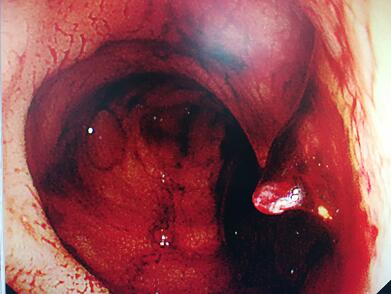

正月十五早上,就在被推进胃镜室前,王老突然面色苍白,排出暗红色的血便近500ml。胃镜室王宏利主任亲自为王老做了细致的食管、胃部检查,让他纳闷的是王老的食管和胃底部等常见出血部位虽有静脉曲张,但却没有破裂的痕迹,胃内也未发现血液,这是怎么回事?

王宏利主任当即决定再为王老做结肠镜检查,查找出血部位。终于,在老人的直肠上发现了“罪魁祸首”——一个直径3、4毫米,绿豆大小的破溃口,经过冲洗、止血、修补等镜下治疗,王老转危为安,被送回了病房。“当了20多年肝病医生,肝硬化并发上消化道出血十分常见,可这种并发直肠出血的病例简直就是凤毛麟角”王宏利主任不无感慨地说。